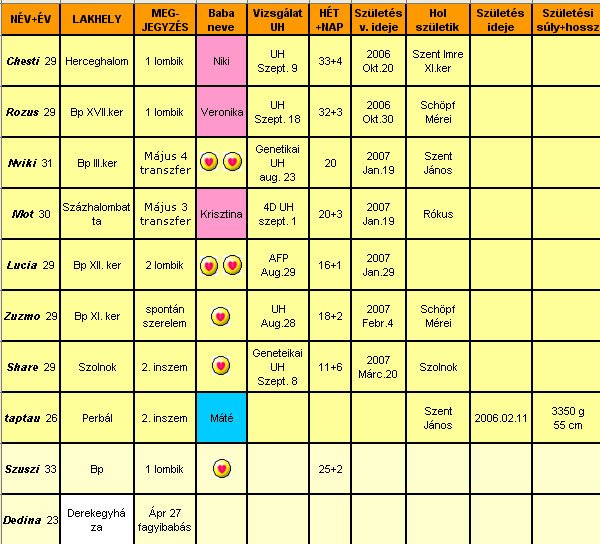

Lányok, Fiúk! Gratulálok a kislányokhoz és vegyes párosokhoz! Nagyon szép neveket választottatok.

Mi is eldöntöttük a neveket. Apa úgy érezte, amíg nincs neve a babának, nem tud vele megfelelően kommunikálni. Luca és Máté a választásunk. Látom, hogy a Máté népszerű a BMC-s kismamák körében.

Chesti, én ma vagyok 12+0, javítsd légy szíves a táblázatban. Legközelebb szeptember végén megyek majd uh-ra, és október 5-ére terveztük be a védőnővel az AFP-t.